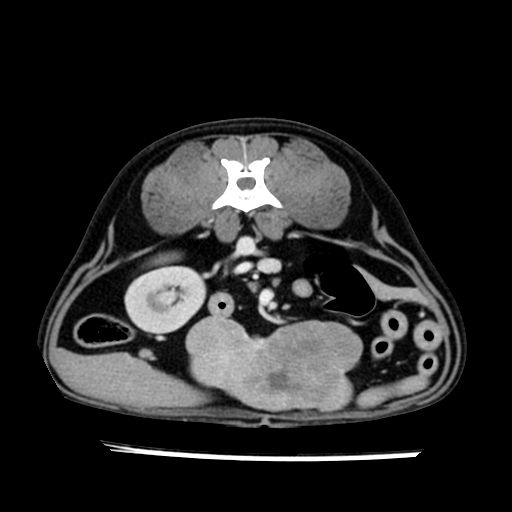

prescritto esame TAC

sequenza immagini limitata al fegato reni e surreni

le immagini ecografiche rispetto alla tac datano circa 7 mesi prima ,le surrenali sono normali nonostante il test acth sia risultato positivo .all’esame TAC dopo diversi mesi risultano aumentate armonicamente nel volume e si individua un forte sospetto di adenoma ipofisario .

sospetto adenoma ipofisario vs. meno probabilmente meningioma della base; intertiziopatia polmonare; lesione espansiva epatica, verosimilmente del lobo laterale sinistro, di sospetta natura neoplastica; lesioni spleniche di natura da definire; iperplasia/ipertrofia delle ghiandole surrenali, bilateralmente; vertebra di transizione del rachide toracico; tenosinovite cronica del muscolo bicipite brachiale di destra.